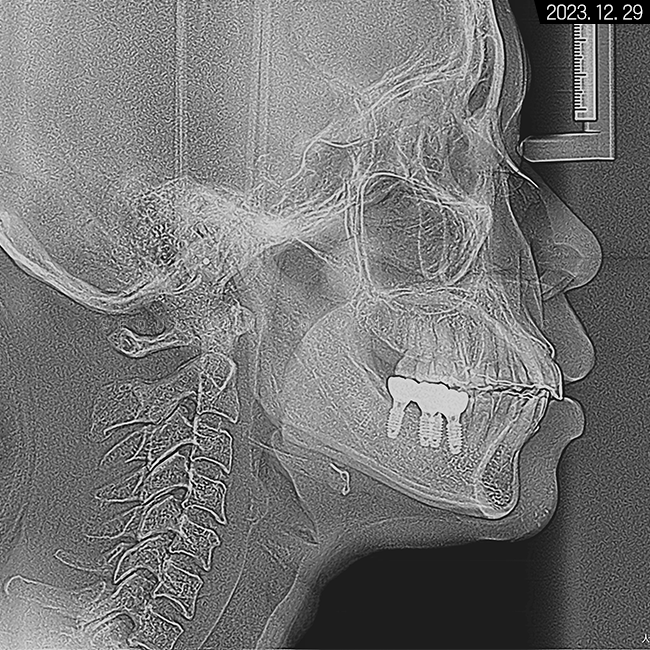

세팔로 사진으로는

잇몸과 치아 전돌 양상이 보이고

에스테틱 라인을 과하게 넘어가 있다는 것을

알 수 있었습니다.

계측점을 분석해 본 결과 정상 범주로 넣기 위해서는

치아 후방 이동이 상당히 필요한 경우였습니다.

세팔로 사진으로 보면 전돌 해소가

더 확실하게 된 것을 볼 수 있어요.

에스테틱 라인도 좋아지고

전체적으로 부드러워진 비율이 나타나고 있습니다.

입술이 예전보다 슬립한 형태가 되기도 하셨고요.